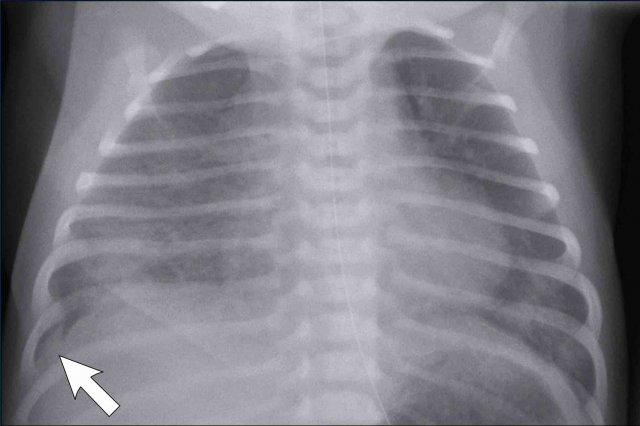

Trẻ sơ sinh 41 tuần tuổi thai. 24 giờ tuổi.

Suy hô hấp, không hỗ trợ thở máy

Image

- Marked

hyperinflation of both lungs - Increased

vascular markings and interstitial markings - Some interfissural fluid (arrow).

Spontaneous improvement within 48 hours.